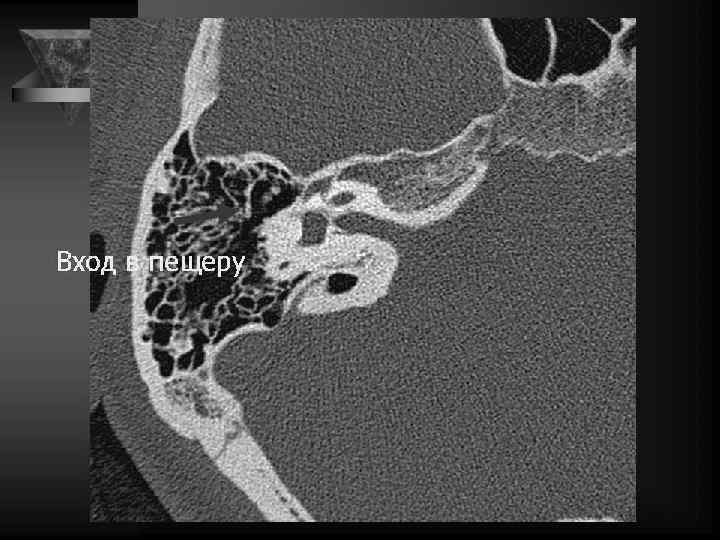

Сосцевидная область • Пневм-я сосц. отростка и степ. ее выраж-ти. • Содержимое сосцевидных ячеек (воздух, жидкость, мягкая ткань). • Положение сигмовидного синуса. • Состояние костных трабекул: интактные, разрушенные. • Наружная поверхность сосцевидного отростка. • Поверхность сосцевидного отростка, обращенная к задней и средней череп. ямкам • Положение вертикальной части канала лицевого нерва и ее целостность.

Внутреннее ухо и верхушка пирамиды • Улитка: деминерал-я костной капсулы, спирал-й канал улитки и его просвет, оссификация • Преддверие и полукружные каналы, интактные стенки, оссификация • Внутр. слух. проход: расширение, неровн-ть контура, деструкция кости, стеноз • Канал лицев. нерва до коленч. ганглия. • Водопровод преддв-я и водопр. улитки. • Верхушка пирамиды: губчатая или пневматизирована, наличие секрета, наличие образований